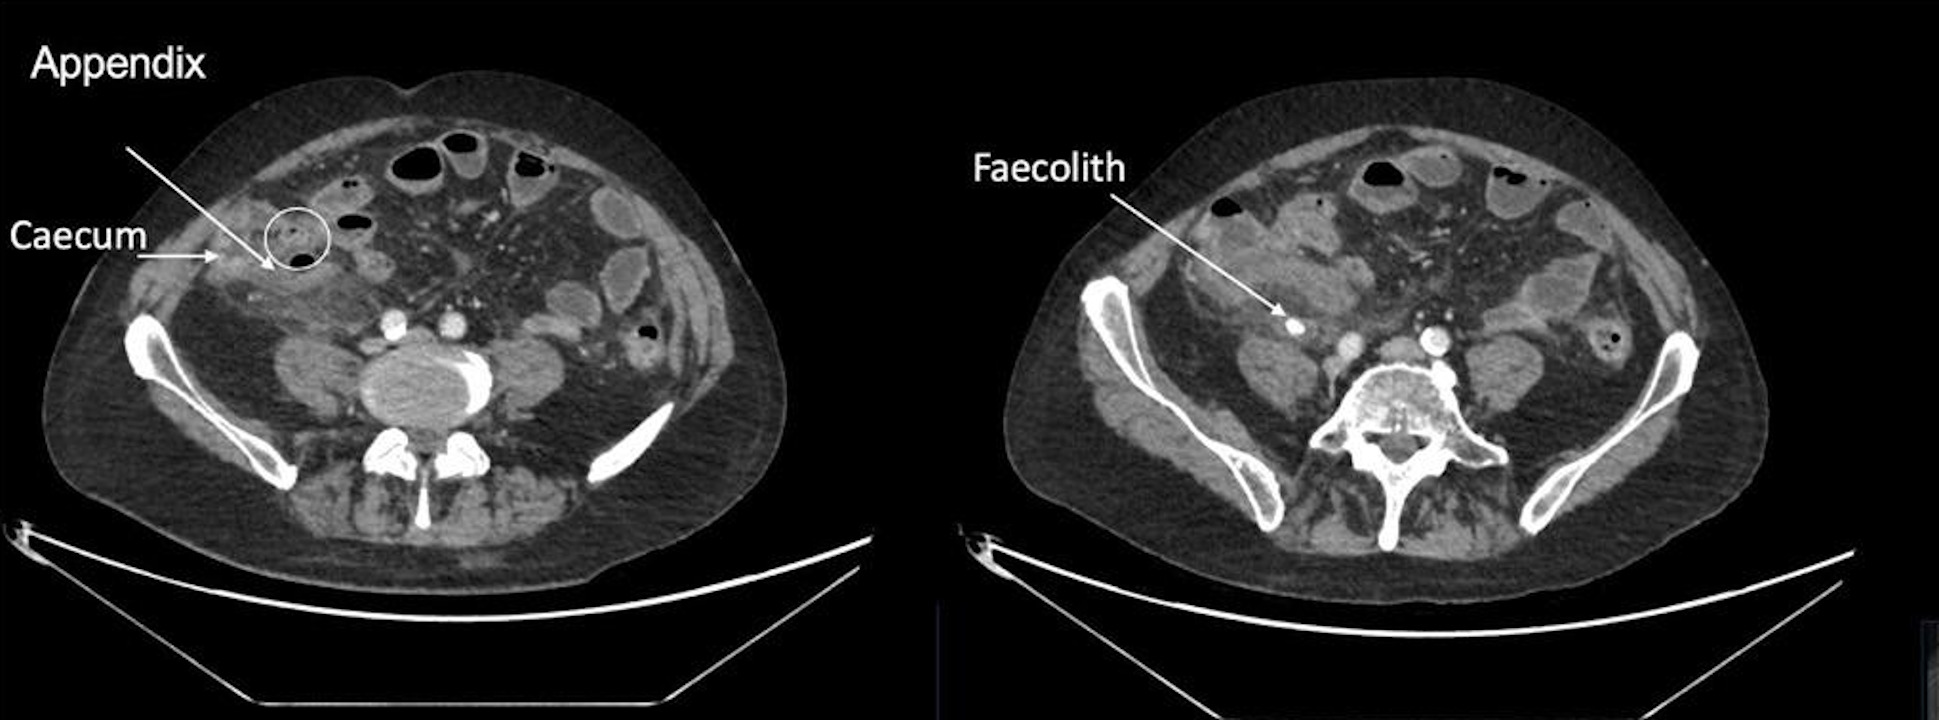

Комп'ютерна томографія апендициту в чоловіка та феколіта — каменя з калу. Kasim et al. / BMJ Case Reports, 2025

Спершу лікарі хотіли провести операцію лапароскопічним методом: з мінімальним надрізом і введенням інструментів крізь отвори. Однак через ускладнення операцію довелося проводити лапаротомічним методом, розрізаючи стінку черевної порожнини. Так хірурги виявили в нього розрив одного з двох апендиксів і феколіт — камінь, утворений із калу. Після операції чоловік приймав антибіотики, ліки для зменшення запалення та артеріального тиску, а виписали його за два тижні після видалення апендиксів. Під час обстеження за три місяці після операції чоловік почувався добре та не мав ознак ускладнень.